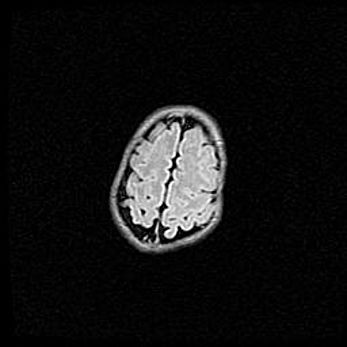

Церебральная ишемия II.

Возраст: 5 дней

Вес: 3400 г

Пол: женский

Окружность головы: 35 см

Срок гестации: 39 недель

Церебральная ишемия – это заболевание, характеризующееся недостаточностью (гипоксией) либо полным прекращением (аноксией) снабжения мозга кислородом по причине закупорки одного или нескольких сосудов. Это приводит к  что метаболическим расстройствам различной степени тяжести в тканях головного мозга, развитию коагуляционных некрозов и гибели нейронов.